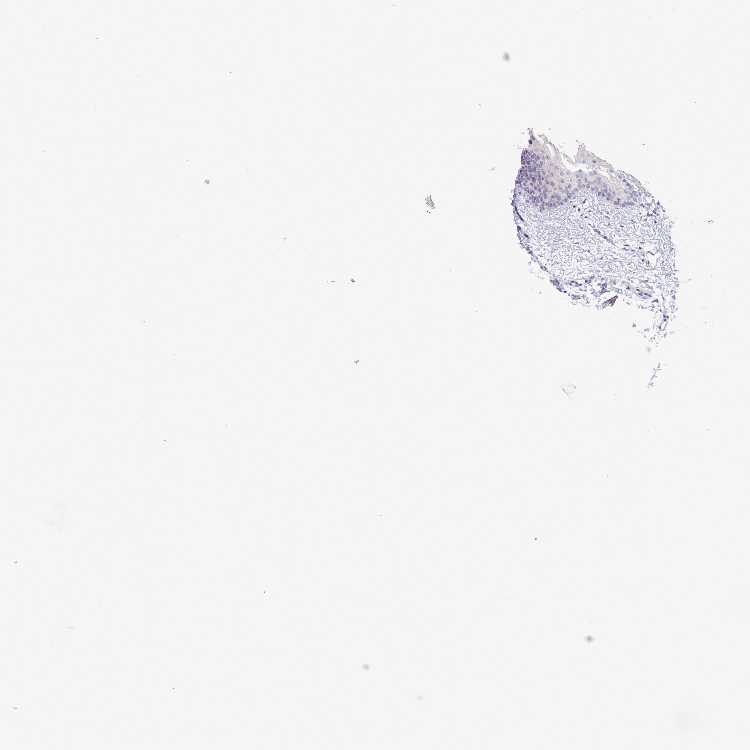

TISSUE PRIMARY DATA ORAL MUCOSA Show tissue menu

ORAL MUCOSA - Antibody stainingi

Antibody staining in the annotated cell types in the current human tissue is reported as not detected, low, medium, or high, based on conventional immunohistochemistry profiling in selected tissues. This score is based on the combination of the staining intensity and fraction of stained cells.

Each image is clickable and will lead to virtual microscopy that enables deeper exploration of all samples and also displays staining intensity scores, fraction scores and subcellular localization as well as patient and tissue information for each sample.

Antibody HPA047216

Squamous epithelial cells Not detected